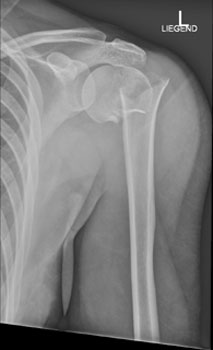

Die Röntgenaufnahme der Schulter in zwei Ebenen ist die Untersuchung der Wahl zur Beurteilung der Knochenstrukturen und der Gelenkstellung.

Hier sehen Sie die Aufnahmen im vorliegenden Fall: